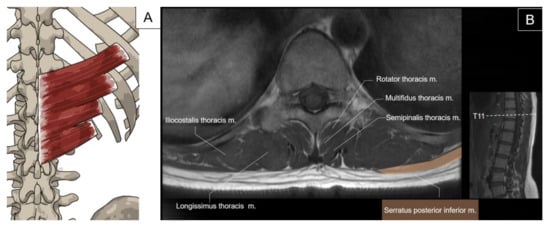

5.1. Iliocostalis Thoracis, Longissimus Thoracis, Semispinalis Thoracis, and Thoracic Multifidus

5.1.1. Anatomy

5.1.2. Sonographic Scanning

5.1.3. Clinical Relevance